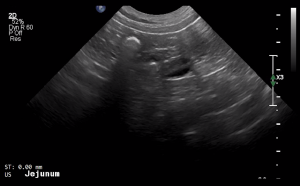

SIMON Ultrasound Database

This ultrasound database is a free resource for students and doctors!

Our collection includes videos of dogs, cats, horses, cows, humans, and many other species!

–Canine and Feline abdominal ultrasound videos were generously provided by the Cummings School of Veterinary Medicine at Tufts University.